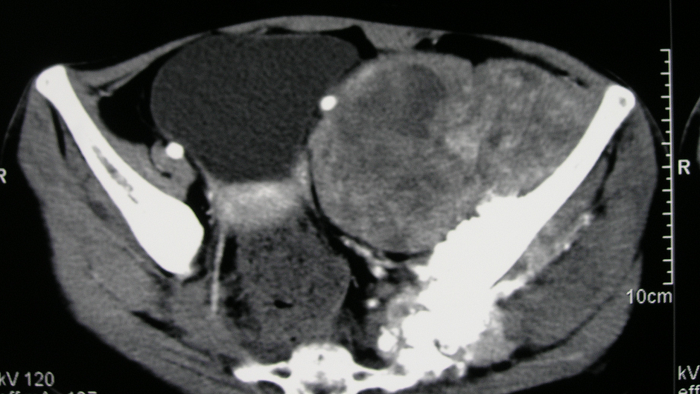

6、病例6:女 18岁 左半骨盆骨肉瘤,全身及肿瘤局部选择性动脉灌注大剂量化疗后行肿瘤切除人工半骨盆假体置换术

图 34、35、36 术前CT:肿瘤体积巨大,压迫

输尿管、膀胱等盆腔脏器